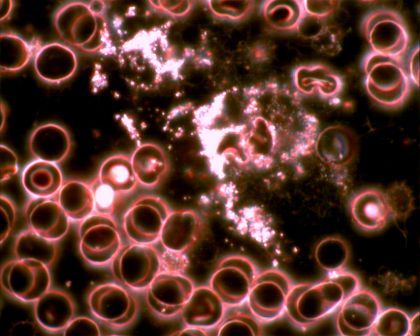

Sötétlátóteres technikával készített élő vércsepp-analízisről fényképek

széteső fehérvérsejtek